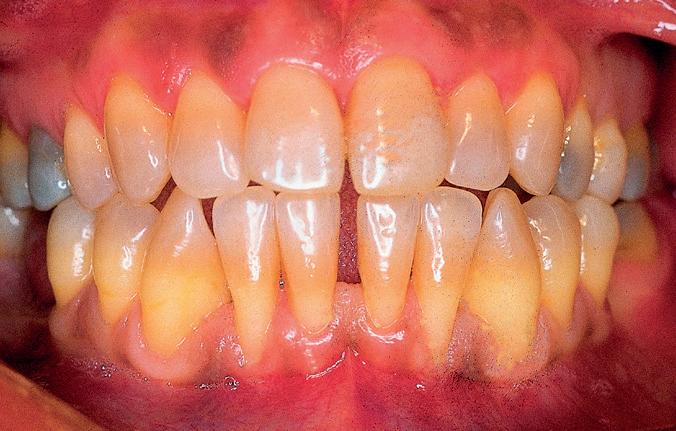

Los injertos profilácticos, se emplean habitualmente en casos de recesiones múltiples, donde no es posible lograr un cubrimiento

Fig 6: Año 1995. Varón de 55 años que presenta recesiones gingivales generalizadas, con pérdida de inserción a nivel interproximal.

radicular completo y donde la estética no es una de las principales preocupaciones para el paciente (Fig nº 6). A diferencia de los injertos terapéuticos, los injertos profilácticos no pretenden cubrir la superficie radicular expuesta. El objetivo es aumentar la cantidad de encía insertada existente, para evitar el avance de las recesiones. Por lo tanto, se trata de poner un stop al avance de la recesión sin que se pretenda, en ningún momento, modificar la ubicación del margen gingival.

Se realizó un autoinjerto libre epitelizado submarginal, es decir, respetando la pequeña banda de encía queratinizada existente, con la técnica de injerto en acordeón que se extendió de 33 a 43. La gura nº 7, muestra la cicatrización temprana. Como era de esperar, se ha logrado aumentar la cantidad de encía insertada,

por debajo del margen gingival, situándose éste en su posición original. Lo llamativo de este caso es que, transcurridos 12 años, la encía ha migrado hacia incisal y ha cubierto parcialmente las super cies radiculares expuestas (Fig nº 8). Es curioso observar cómo con el transcurso de los años se ha remodelado el tejido blando, otorgándole un contorno y un volumen muy diferentes a los que se aprecian en la gura nº 7.

Fig 7: Cicatrización temprana. Se realizó un autoinjerto submarginal. Se aprecian de manera nítida los límites que de nen el injerto y el margen gingival que ha sido respetado. El injerto, ha logrado crear una adecuada dimensión volumétrica de encía insertada y ha profundizado el vestíbulo. En ningún momento se ha pretendido cubrir la super cie radicular.

Fig 8: Resultado a los 12 años. Compárese con la Fig 7. El injerto ha sufrido un profundo remodelado con el paso del tiempo, modi cándose su contorno, volumen y cubriendo parcialmente las super cies radiculares expuestas. ¿Cómo es posible que ocurra este fenómeno con un injerto submarginal?